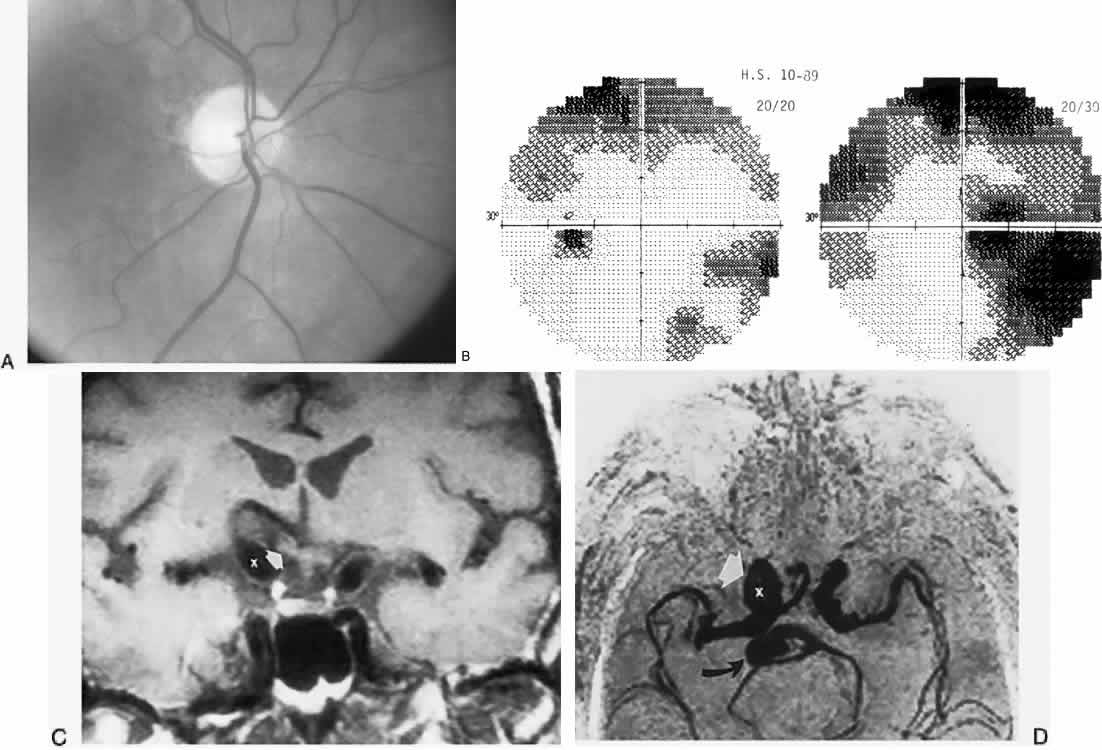

The retinal variety may be admixed in a person who suffers the more conventional attacks of migraine. It is presumed that vasospasm in the retinal circulation determines transient hypoxia, perhaps somewhat similar to the visual cortical event. On rare occasions, the fundus has been examined during typical retinal migraine episodes, and arterial constriction has been described. Wolter and Burchfield106 photographically documented such an episode and demonstrated mild “retinal edema”; vessel narrowing is also evident (Fig. 8). Fortunately, permanent complications of retinal migraine are rare. These may take the form of central retinal artery occlusion or ischemic papillopathy (see Volume 2, Chapter 16); nerve fiber bundle visual field defects may be demonstrated (Fig. 9).

Fig. 9. An 18-year-old student with recurrent episodes of left retinal migraine. After a typical attack, he noted an inferior field defect. A. Fundus shows a defect in the superior arcuate nerve fiber bundle (between arrows: compare fiber layer below disc). B. Visual field defect corresponds to a retinal nerve fiber layer defect.